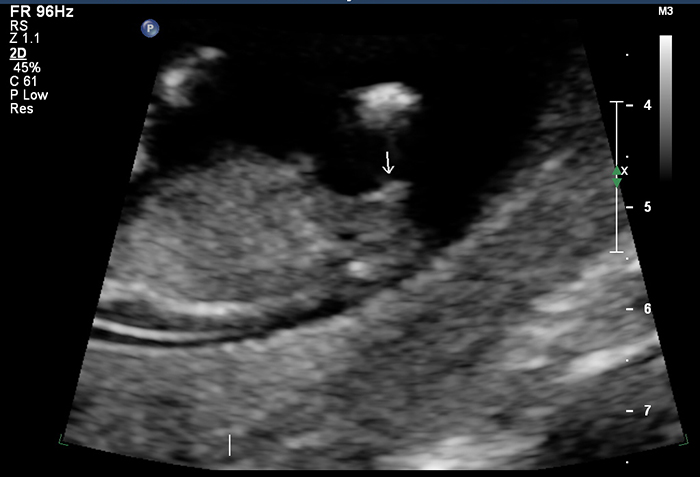

The full body shot. There's no real view of the nub here.

Zoomed in nub shot.